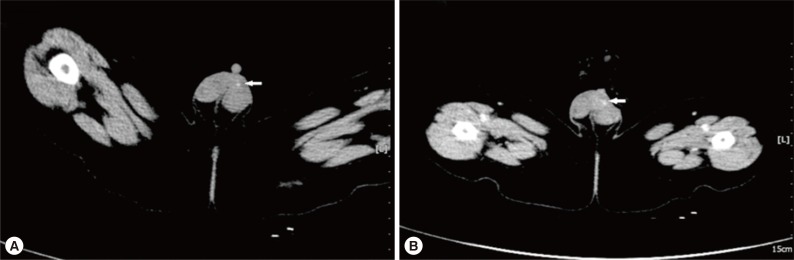

A 5-month-old boy was found to have an asymptomatic left scrotal mass for 3 months. The mass was soft, non-tender and without overlying scrotal skin abnormality. Ultrasound examination identified that the left scrotal wall was thickened with a mixed-echogenicity mass measuring 11×3 mm, which had an obscure boundary and increased blood supply on color Doppler (Fig. 1). The mass was thought to be inflammatory in origin, and observation was recommended. However, repeat ultrasound examinations demonstrated the mass to be increasing in size. The last ultrasound examination revealed a 19×9 mm hetero-echogenic mass with ill-defined margins. Physical examination demonstrated a flat mass of the left scrotum measuring 20×10×3 mm, with non-homogeneous consistency, ill-defined borders and no tenderness. CT showed a mass of 12×9 mm anterior to the left testicle, with heterogeneous density and punctate calcifications (Fig. 2A) and obvious enhancement after administration of contrast agent (Fig. 2B), which was diagnosed as a left testicular teratoma. The complete blood count (CBC), electrolytes, and liver function tests were all normal prior to surgery. The eosinophil differential count was 6% (normal range: 0.5 to 5%). No parasite eggs were found on routine stool testing. The α-fetoprotein (AFP), 19.5 µg/L (normal <20 µg/L), and human chorionic gonadotropin (HCG), 2.01 µg/L (normal <3.1 µg/L), were both normal.

Ultrasound is often used for evaluation of superficial subcutaneous masses, including the scrotum. The ultrasound characteristic of internal serpiginous tubular structures suggests sparganosis, but this can also be seen in radiation edema and superficial phlebitis [9,11,14]. In this case, multiple ultrasound examinations demonstrated a heterogeneous echogenic mass of the scrotal wall without internal anechoic serpiginous tubular structures. Therefore, ultrasound has limitations in the differential diagnosis of scrotal sparganosis [11]. The CT findings of scrotal sparganosis are similar to the reported triad manifestations of cerebral sparganosis: low density mass, punctate calcifications, and nodular or irregular enhancement [16,17]. The CT scan revealed a heterogeneous density mass of the scrotal wall with punctate calcifications on plain CT in our patient (Fig. 2A) and obvious enhancement on contrast-enhanced CT (Fig. 2B), which was misdiagnosed as a scrotal teratoma.